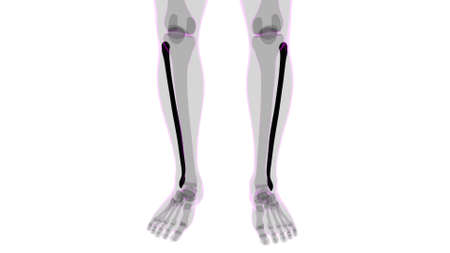

3D Illustration Human Skeleton Anatomy Bones of Tibia Fibula

Transparent view of fibula, tibia and foot bones of a man on white isolated background